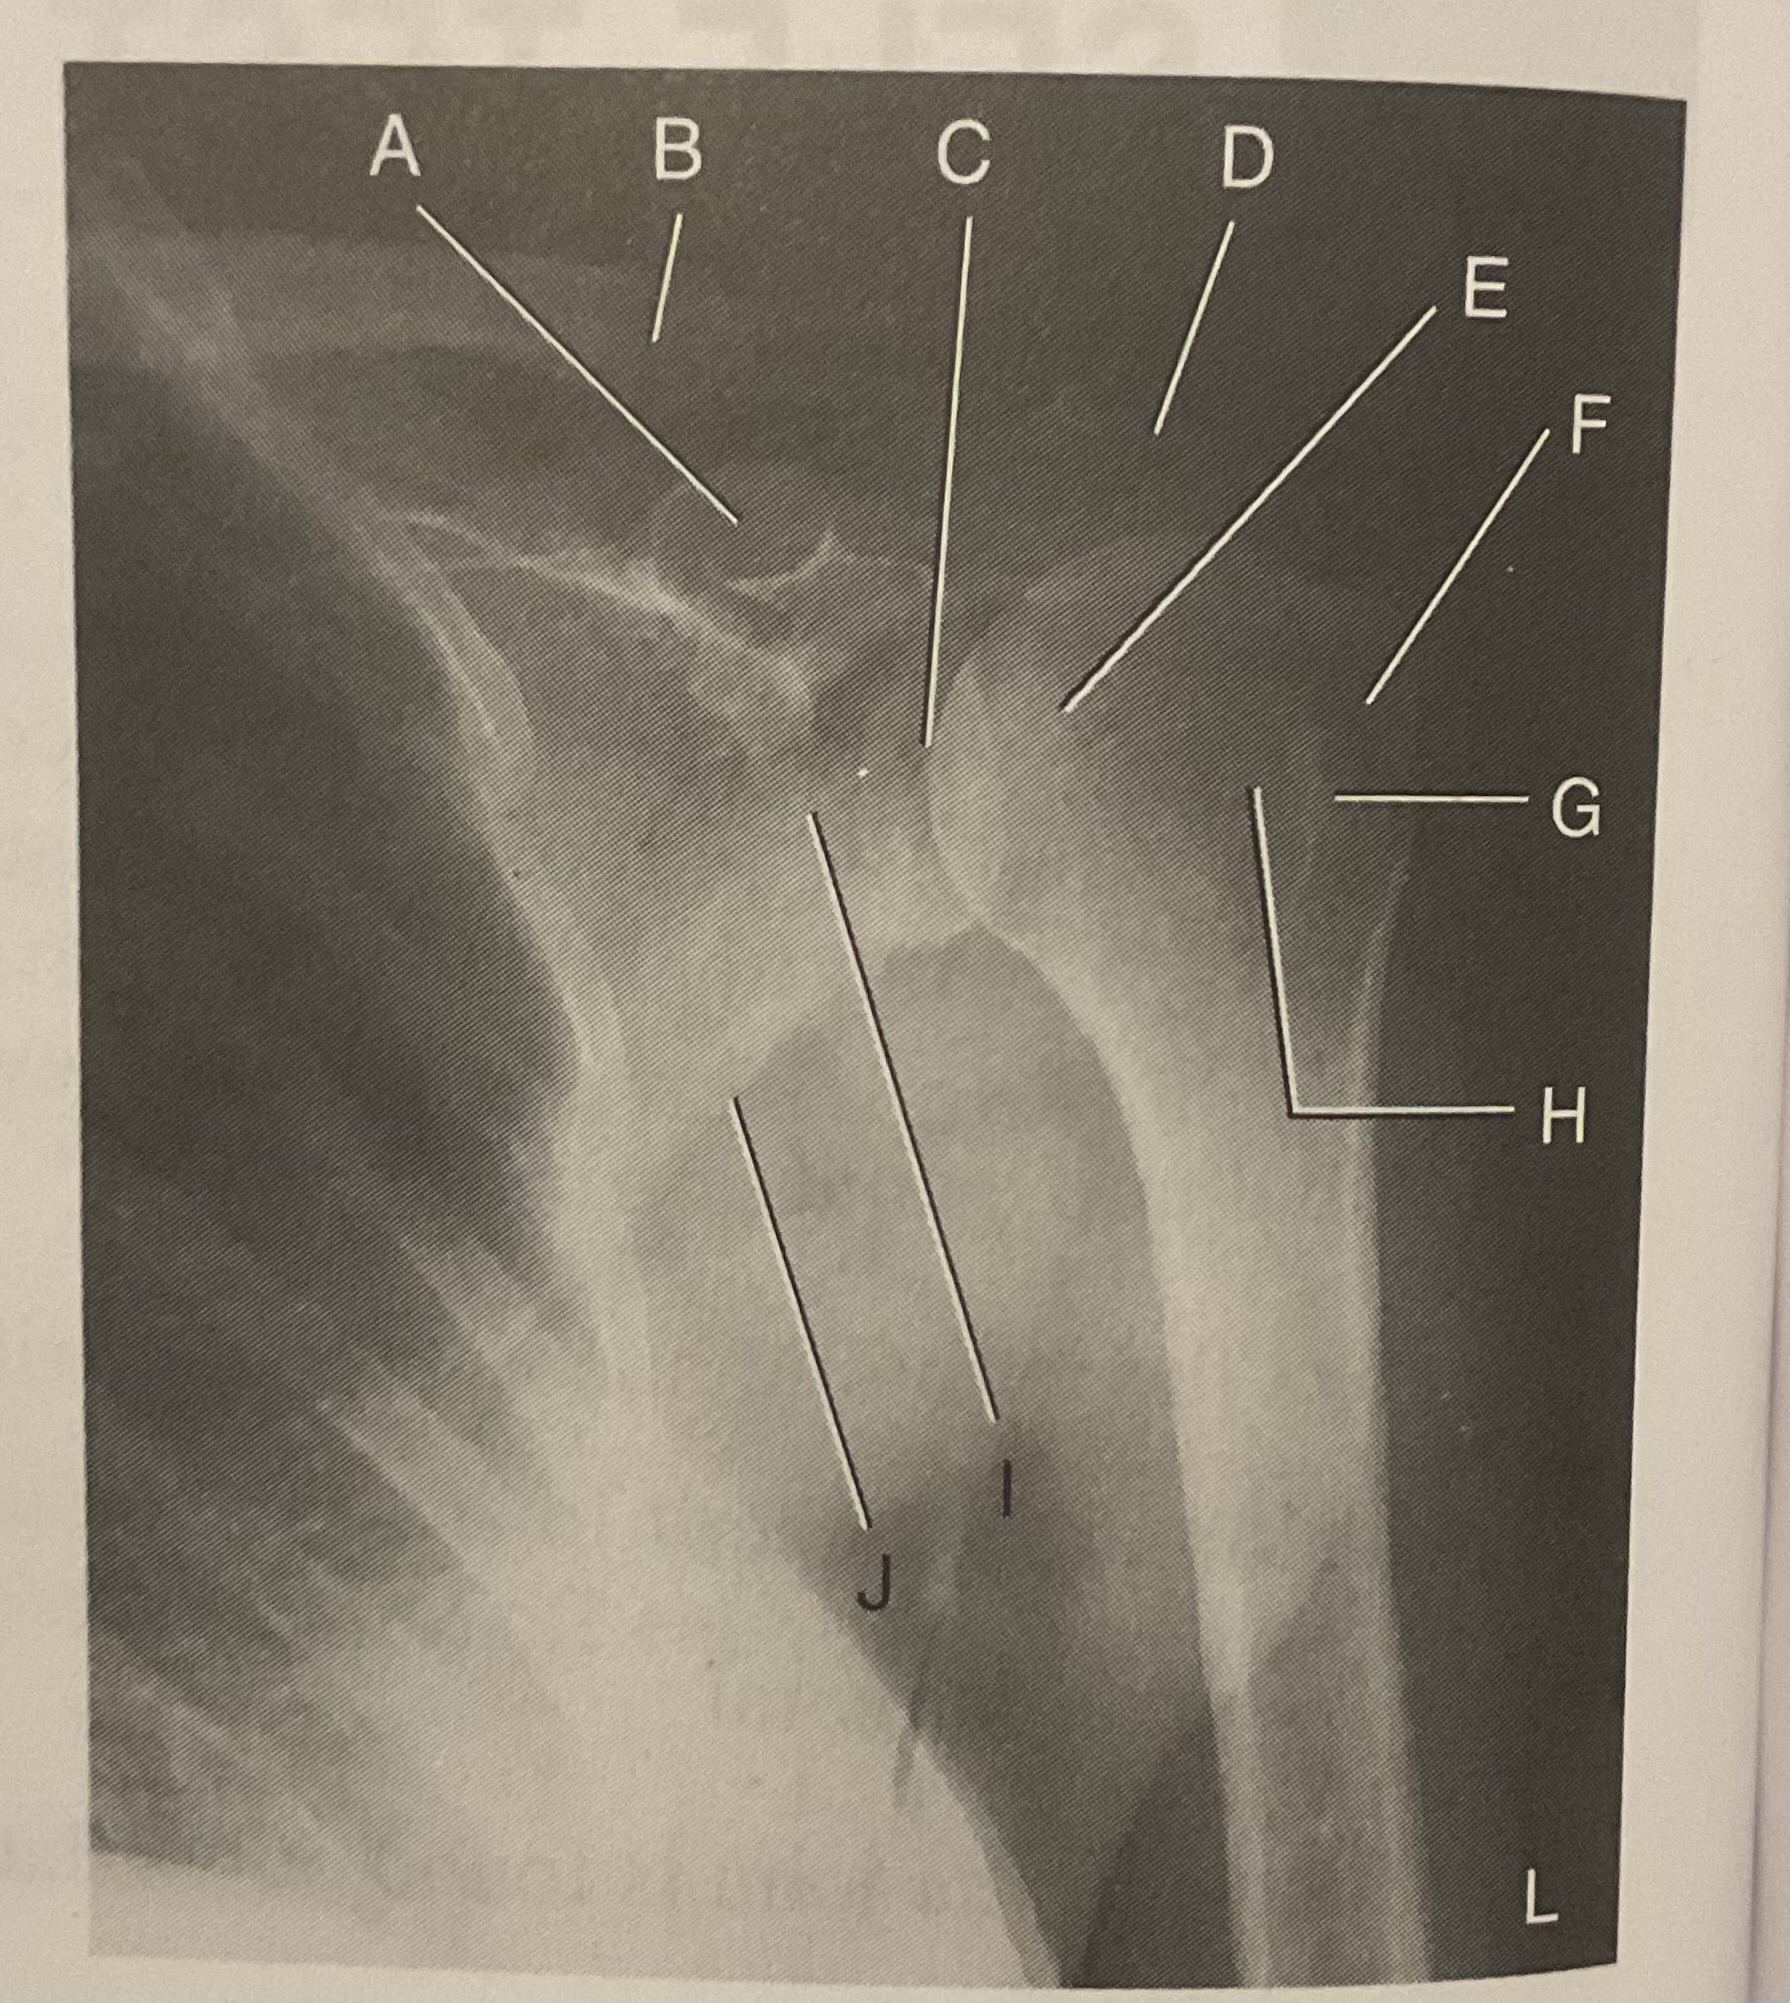

A?

Coracoid process

B?

Clavicle

C?

Scapulohumeral joint

D?

Acromion of scapula

E?

Head of humerus

F?

Greater tubercle

G?

Intertubercular sulcus

H?

Lesser tubercle

I?

Neck of scapula

J?

Lateral (axillary) border of scapula

What AP projection does this image represent?

External